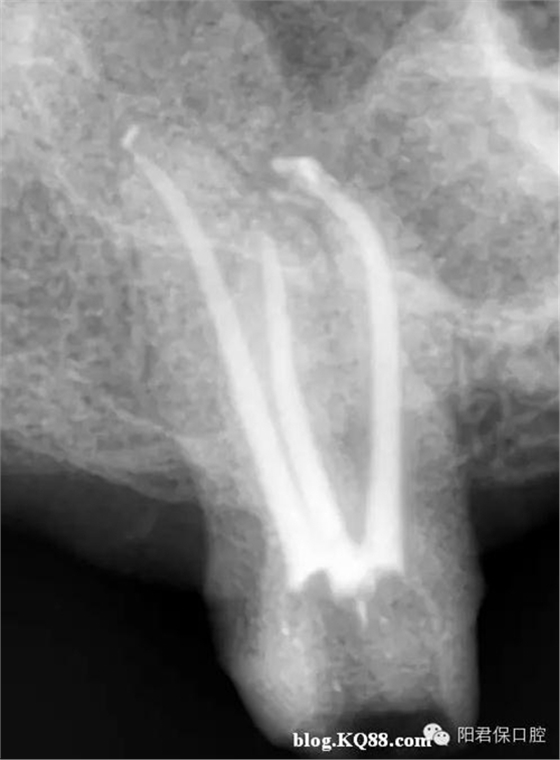

患者:姜XX 性別;女 年齡:65 根據(jù)齲壞程度、患者的癥狀、修復需要,且對收費及牙髓處理均征得同意后第一次行右下4、5,左下4、5、6;第二次行左下2,右下2 ,右上7一次性根管治療術(shù)。

術(shù)后見右下4,左下4均有側(cè)支充填,且位置對稱,左下6近中根中部有側(cè)支;左下5、左下6遠中根管均多個開口。

熱牙膠垂直加壓后有封閉劑和牙膠超填,但無術(shù)后反應。